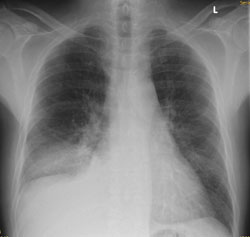

Radiologie Quiz 47

Ein 68-jähriger Patient mit chronischer Niereninsuffizienz und hypertensiver Herzerkrankung klagt akutell über zunehmende Dyspnoe. Sie veranlassen ein Thoraxröntgen.

Thorax pa

Welcher Befund liegt vor? (mehrere richtige Antworten möglich)